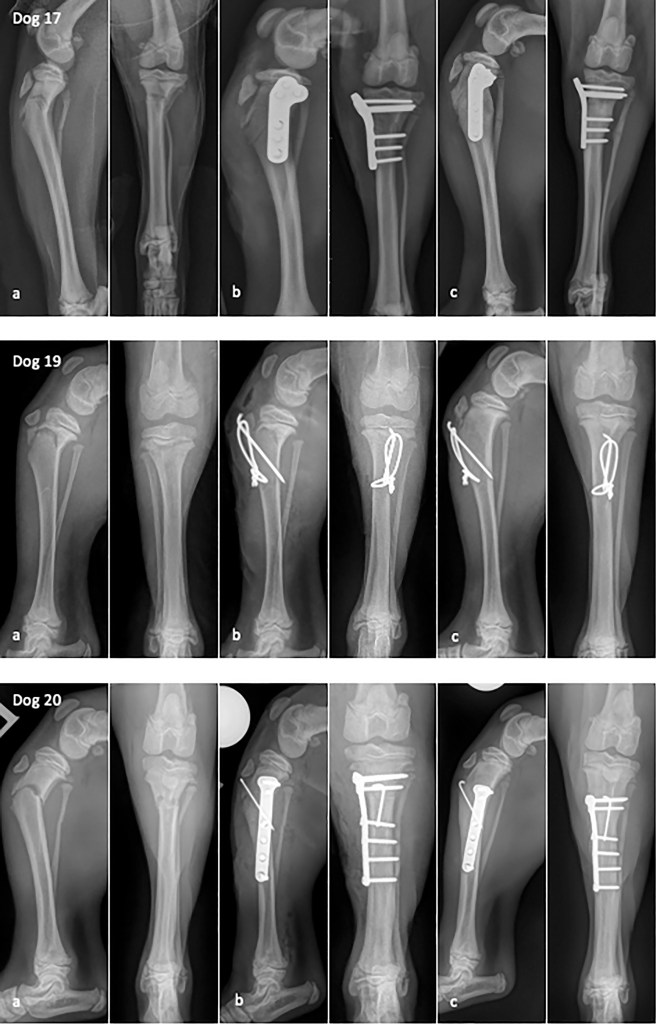

FRAKTURAT ndeshen shpesh ne punen klinike te perditeshme me kafshet e vogla dhe perbejne 13 per qind te rasteve ortopedike tek qente dhe afersisht 40 perqind tek macet. Frakturat diafizare perbejne afersisht 60 perqind te frakturave ne pergjithesi. Nese trajtohen sic duhet keto fraktura, prognoza per sherimin e tyre dhe rikthimin e gjymtyres ne funksion normal eshte e mire. Megjithate, kirurgjia e frakturave mund te shoqerohet me gabime teknike dhe planifikim te pamjaftueshem qe si pasoje kane deshtimin e trajtimit dhe rikorigjimin i cili eshte i kushtueshem dhe traumatik, ose ne rastin me te keq ne amputimin e gjymtyres ose eutanazine. Per kete arsye eshte thelbesore qe kur trajtohen paciente me fraktura, kirurgu te njohe parimet e trajtimit, si dhe njohuri teknike per te aplikuar nje game te plote te teknikave kirurgjikale. Ky material paraqet planifikimin e nevojshem dhe teknikat e disponueshme per trajtimin e frakturave diafizare.

Historikisht, ortopedet jane perpjekur qe gjate kirurgjise se frakturave te rikthejne formen anatomike normale te kockes. Per frakturat diafizare, kjo do te thoshte nje rindertim i plote i cilindrit te kockes. Megjithese kjo gje mund te conte ne avantazhe biomekanike, nderkohe qe pesha e ushtruar ndaj kockes gjate mbajtjes se peshes ne periudhen postoperatore ishte e ndare midis implanteve dhe kockes se rindertuar, gradualisht u be e qarte se kishte nje kosto biologjike ne rindertimin e frakturave te thermuara. Manipulimi i tepert dhe diseksioni i nevojshem per te aritur rindertimin demtonin ngjitjen e indeve te buta me kocken, devitalizonin kocken dhe se fundmi ngadalesonin sherimin. Per shkak te kohezgjatjes se madhe te nderhyrjeve kirurgjikale viheshin re nje shkalle e larte komplikimesh dhe infeksionesh si dhe prania e fragmenteve te pa vaskularizuar.

Njohja e biologjise se sherimit te frakturave

Kohet e fundit, eshte provuar se ruajtja e kujdesshme e bilogjise natyrale te vatres se fraktures mund te coje ne sherimin me te shpejte. Duhet te behet cdo perpjekje per te ruajtur hematomen e fraktures, e cila permban faktore rritjeje osteogjenik te rendesishem, si dhe te ruhen ngjitjet e indeve te buta dhe vaskularizimi i fragmenteve kockore. Sherimi dytesor i kockes realizohet permes prodhimit te kallos, gje qe ka cuar ne lindjen e konceptit te “fiksimit biologjik te fraktures”. Megjithese ky eshte nje lloj gabimi ne emertim, pasi te gjitha frakturat sherohen biologjikisht, termi eshte perdorur per te pershkruar nje strategji per fiksimin e frakturave duke u bazuar ne teknika minimalisht invazive.

Ne rastet e frakturave te thermuara, implantet perdoren ne menyre te tille qe te krijojne nje “ure” mbi vatren e fraktures, duke shmangur manipulimin e cdo fragmenti. Kjo gje arrihet permes teknikes “hap por mos prek”, ne te cilen fraktura ekspozohet ne rruge kirurgjikale por fragmented e kockes nuk manipulohen, ose permes reduktimit plotesisht te mbyllur kur vatra e fractures nuk ekspozohet. Gjatesia e kockes rivendoset dhe artikulacionet vihen ne nje drejtim, dhe me pas implantet vendosen ne fragmentet kryesore te fractures proksimalisht dhe distalisht, duke kaluar mbi vatren e fraktures. Duke perdorur kete strategji, parimet origjinale AO perseri mund te aplikohen, por ndryshe nga e kaluara kur theksi vihej mbi rindertimin e sakte me kosto mbi ruajtjen e biologjise se fraktures, tashme theksi vihet ne ruajtjen e biologjise megjithese duhet qe te sakrifikohet disi saktesia e rindertimit anatomik te kockes. Ne pergjithesi kjo strategji aplikohet vetem tek frakturat diafizare. Frakturat artikulare perseri kerkojne rindertim te sakte anatomic te fragmenteve per te mundesuar funksionin e siperfaqeve artikulare si dhe mundesimin e sherimit primar te kockes.